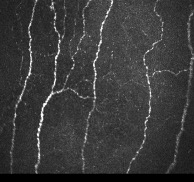

Différence de taille d'incision entre la découpe d'un capot en LASIK (section sur 24mm) et la découpe d'une mini incision en SMILE (section sur 3mm)

Les nerfs cornéens sont sectionnés sur une plus petite zone en SMILE à la même profondeur

LASIK

SMILE